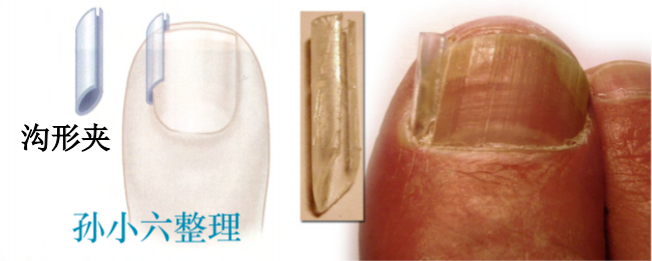

保守治疗